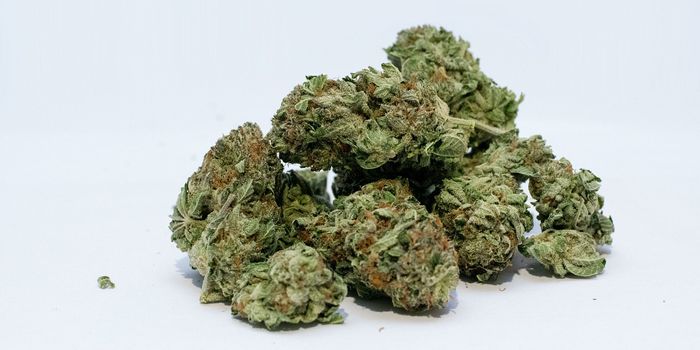

SEP 12, 2024Health & MedicineA study published in Addictive Behaviors reported that cannabis and tobacco use is increasing among older adults. The fi ...

SEP 10, 2024Health & MedicineA study published in ACS Pharmacology & Translational Science indicated that long-term THC treatment can initially e ...

SEP 05, 2024Cannabis SciencesUse of cannabis and hallucinogens remained at historically high levels in 2023 among adults aged 19- 30 years and 35-50.

SEP 05, 2024Cannabis SciencesWhat influence does cannabis legalization, whether medical or recreational, have on mental health prescription medicatio ...

SEP 04, 2024Cannabis SciencesCannabis use is relatively common among patients thinking about getting plastic surgery and is linked to higher urine ni ...

AUG 30, 2024Cannabis SciencesA study published in Ophthalmic and Physiological Optics examined the connections between John Lennon’s myopia, co ...

AUG 29, 2024Cannabis SciencesPatients with a recent history of recreational drug use are three times more likely to have a repeat serious cardiovascu ...

AUG 28, 2024Cannabis SciencesRecent and frequent cannabis use and cannabis use disorder (CUD) are linked to higher levels of workplace absenteeism.

AUG 22, 2024Cannabis SciencesA new study found that 86% of drug researchers have used drugs such as cannabis in the past, with 47% reporting use in t ...

AUG 22, 2024Cannabis SciencesHow is marijuana use linked to obesity? This is what a recent study published in Cannabis and Cannabinoid Research hopes ...

AUG 22, 2024Cannabis SciencesA study published in Medical Cannabis and Cannabinoids explored optimal trimming conditions that affect the cannabinoid ...

AUG 16, 2024Cannabis SciencesA study published in Scientific Reports is the first human clinical trial to examine the effects of the cannabinoid cann ...

AUG 15, 2024Cannabis SciencesLegalization of cannabis products, including edibles, has coincided with higher rates of older adults visiting the emerg ...

AUG 15, 2024Cannabis SciencesExposure to THC and CBD in the womb leads to abnormal developmental change in rats, including disrupted growth rates and ...

AUG 13, 2024Health & MedicineA recent study published in the journal Cannabis and Cannabinoid Research found that most commercially available cannabi ...

AUG 09, 2024Cannabis SciencesA study published in Medical Cannabis and Cannabinoids indicated that patients reported a decrease in refractory gastroi ...

AUG 08, 2024Cannabis SciencesAn over-the-counter dietary supplement shows promise for counteracting the negative effects of heavy cannabis use among ...

AUG 08, 2024Cannabis SciencesCannabis is linked to both an increased risk of coronary artery disease, and a lower risk of cardiovascular complication ...

AUG 08, 2024Cannabis SciencesA study published in the Journal of Agricultural Hemp Research examined the effect of microbial seed inoculation on cann ...